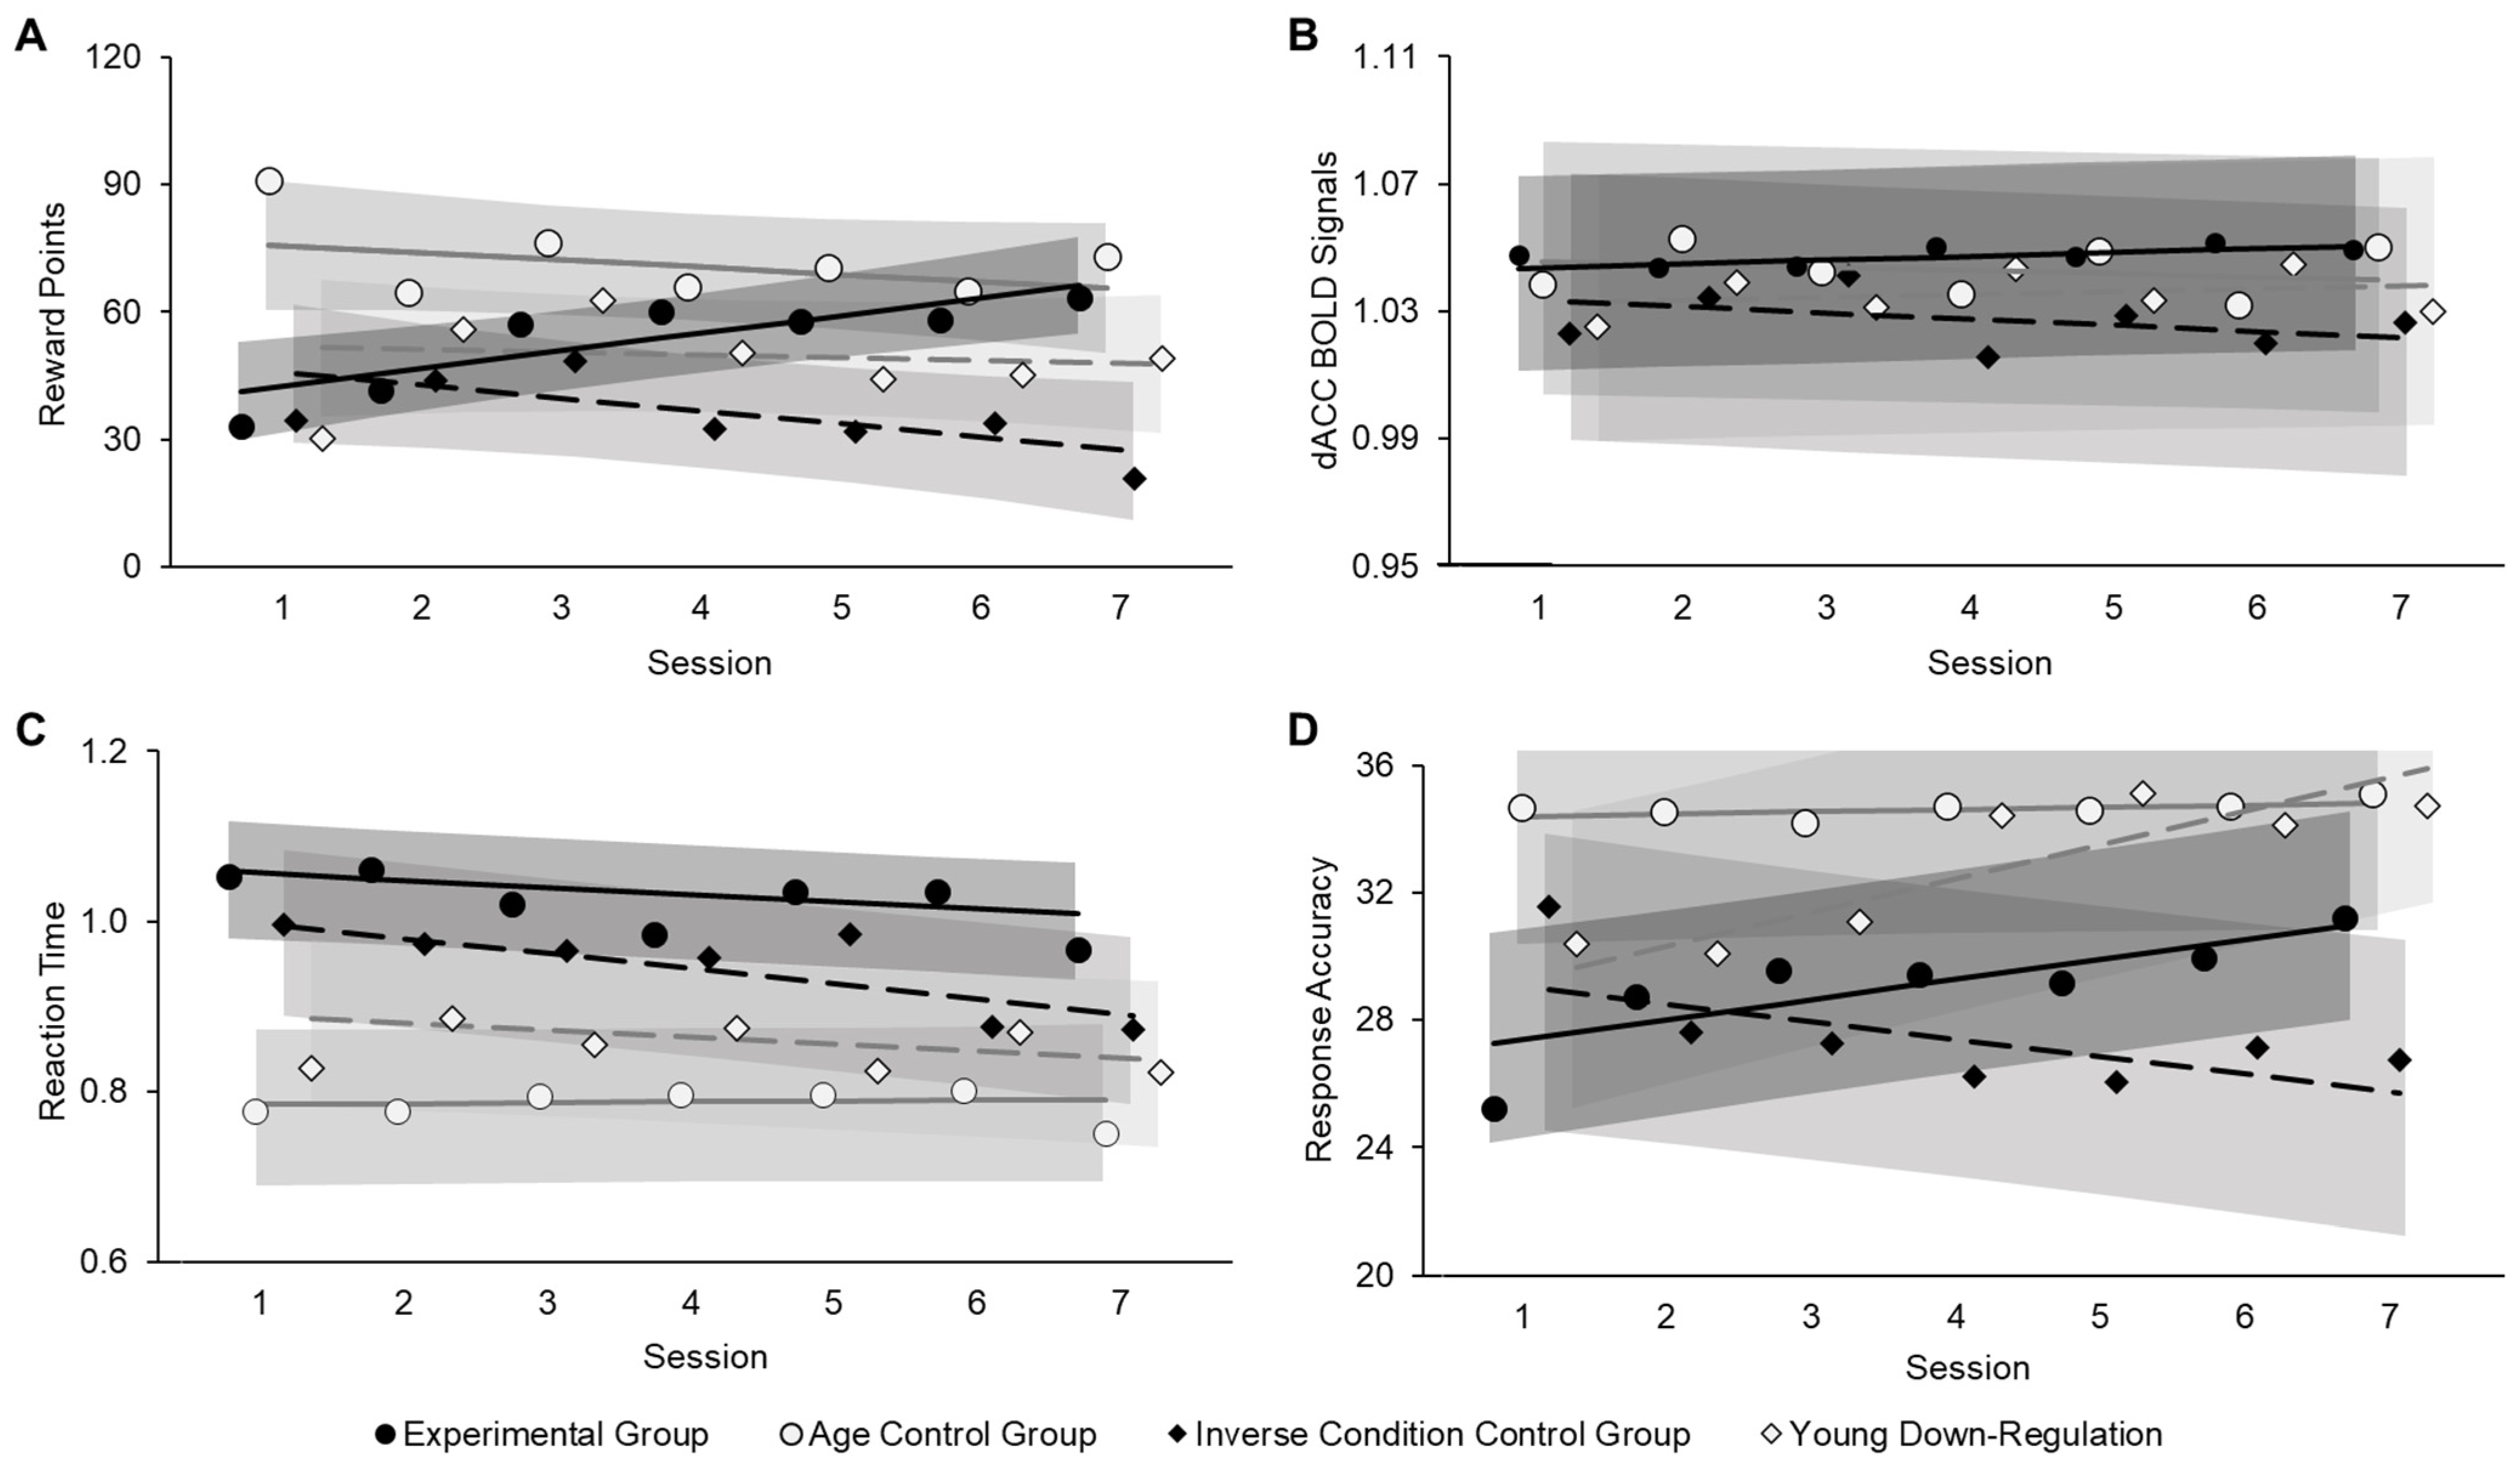

3.2.1. Neurofeedback Training Success (Aim 1)

3.2.2. Behavioral Benefits from Neurofeedback Training (Aim 2)

3.2.3. Follow-Up Brain-Behavior Analysis